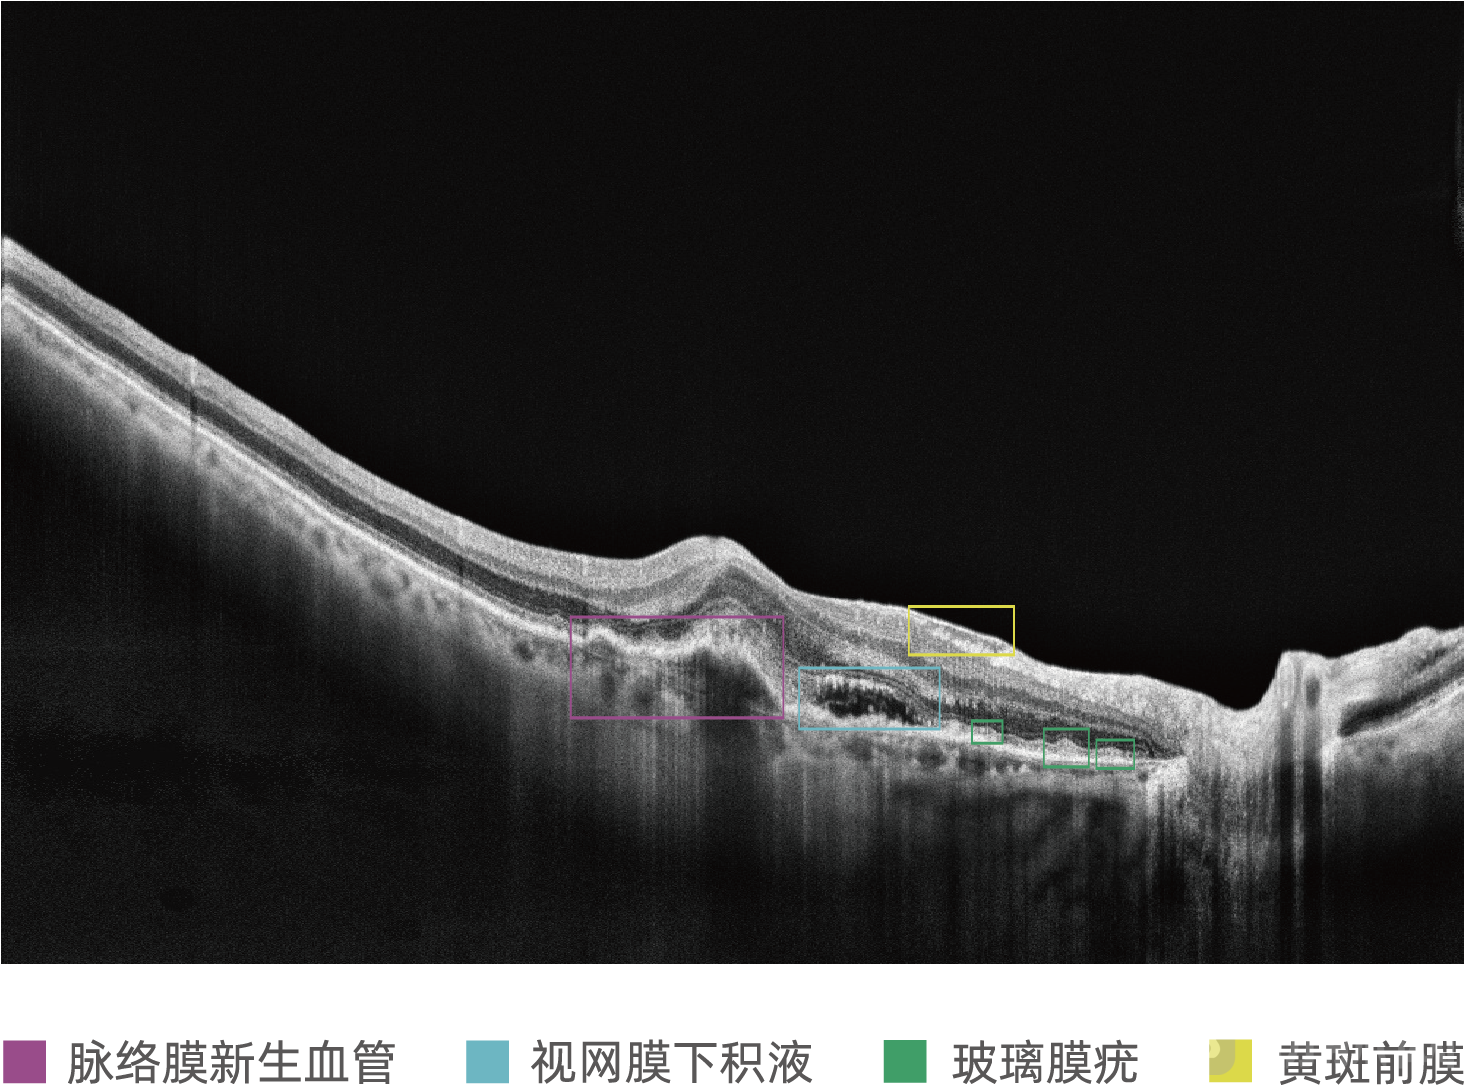

MIAS-3000使用比格威OCT设备采集图像,范围为12 X 9mm,可同时覆盖黄斑与视盘部位;MIAS-3000通过深度学习算法,自动分析OCT切片图像,精准识别玻璃膜疣、积液、新生血管等病灶信息,为50岁及以上患者提供是否存在中期及中期以上年龄相关性黄斑变性的辅助诊断建议。

案例2